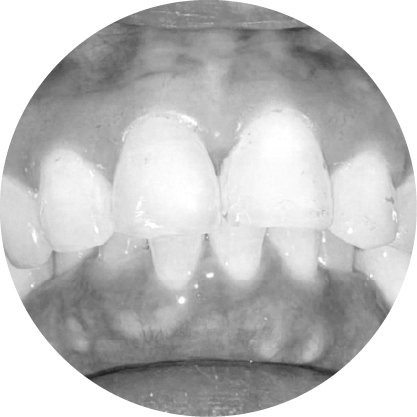

ฟันซ้อน (Overcrowded Teeth)

Creating Space for Crowded Teeth

ฟันเกคือภาวะที่ขากรรไกรมีพื้นที่ไม่เพียงพอ ทำให้ฟันซ้อนหรือเรียงตัวไม่เป็นระเบียบ การรักษาช่วยเพิ่มพื้นที่เพื่อจัดฟันให้เข้าที่อย่างเหมาะสม ส่งผลให้รอยยิ้มดูสวยงามขึ้นและสุขภาพช่องปากดีขึ้นด้วย

ตัวอย่างในชีวิตจริง